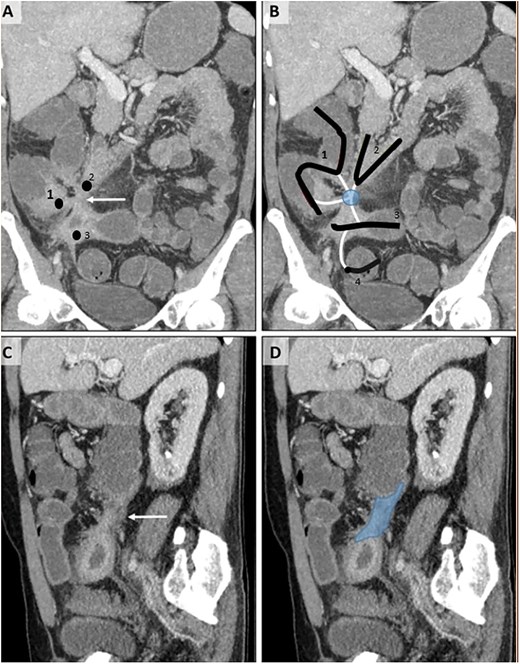

A 54-year-old male patient diagnosed with Crohn’s disease applied to our clinic with complaints of abdominal pain, diarrhea, and ~15 kg weight loss in the last year, which is a significant loss considering his initial weight of 65 kg. The patient had no history of surgery, but it was learned that he had been treated for miliary tuberculosis 2 years ago. Additionally, the patient is receiving medical treatment for Crohn’s disease. Upon examination, there was tenderness in the lower quadrants of the abdomen. Laboratory examinations revealed high C-reactive protein and white blood cell count. Abdominal ultrasonography showed wall thickening in the terminal ileum. Consequently, tomography enterography was performed 1 month after admission. Computed tomography (CT) showed thickening in the terminal ileum wall, an appearance suspicious for fistula between the duodenum and cecum and between the terminal ileum and sigmoid colon, and lymphadenopathy (Fig. 1). To further evaluate the suspected fistulae, colonoscopy was performed within 2 weeks of admission, and fistula orifices were identified in the sigmoid colon and terminal ileum. Following these findings, the patient was scheduled for surgery in the third month after presentation. During this period, the patient received oral antibiotic therapy to control a secondary infection. During the surgery, there were millimetric lesions in the small bowel mesentery that were suspicious for carcinomatosis, and a fistula appearance between the terminal ileum and sigmoid colon and between the cecum and the 2nd–3rd part of the duodenum. Frozen samples were taken from the millimetric lesions due to the preliminary diagnosis of carcinomatosis and were interpreted as benign. Thereupon, the patient underwent ileocecectomy, fistulectomy using linear stapler in the fistulized area in the duodenum and duodenal repair, and primary repair with vicryl in the fistulectomy area in the sigmoid colon (Fig. 2). Postoperatively, the patient was monitored in the intensive care unit for one day. Enteral nutrition was initiated gradually on the third postoperative day, starting with clear fluids and advancing to a soft diet. He was discharged on the 8th postoperative day without complications. Histopathological examination revealed ulcerated clonic mucosa, inflammatory granulation tissue, and fistula formation, consistent with Crohn’s disease. Additionally, biopsy samples were sent for mycobacterial culture to rule out tuberculosis, and the results were negative.

CT enterography examination, coronal (A, B) and sagittal (C, D) MIP (maximum intensity projection) images.Thickening and increased contrast enhancement are observed in the walls of the 2nd–3rd parts of the duodenum (2), terminal ileum (3), and cecum (1) (A). The relationship of these structures, whose lumens are indicated by the same numbers, with the tract-like structures (white lines) of the sigmoid colon (4) — fistulization (circle) — is shown (B). In the sagittal images (C, D), a fistula tract (D, dark area) with a thick wall (C, white arrow) is observed.